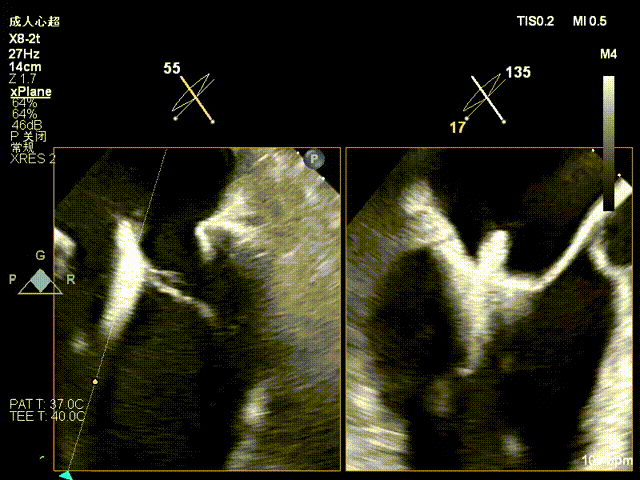

术前Commissural 切面

术前X-plane